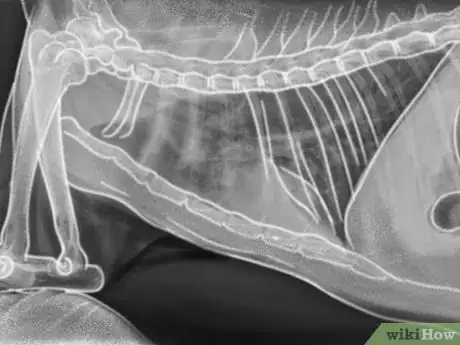

3Notice labored breathing. Pneumonia is also a symptom of toxoplasmosis, although it is less common. If you notice a shortness of breath, wheezing, coughing, and/or shallow, rapid breathing, then your cat may have pneumonia as a result of toxoplasmosis.